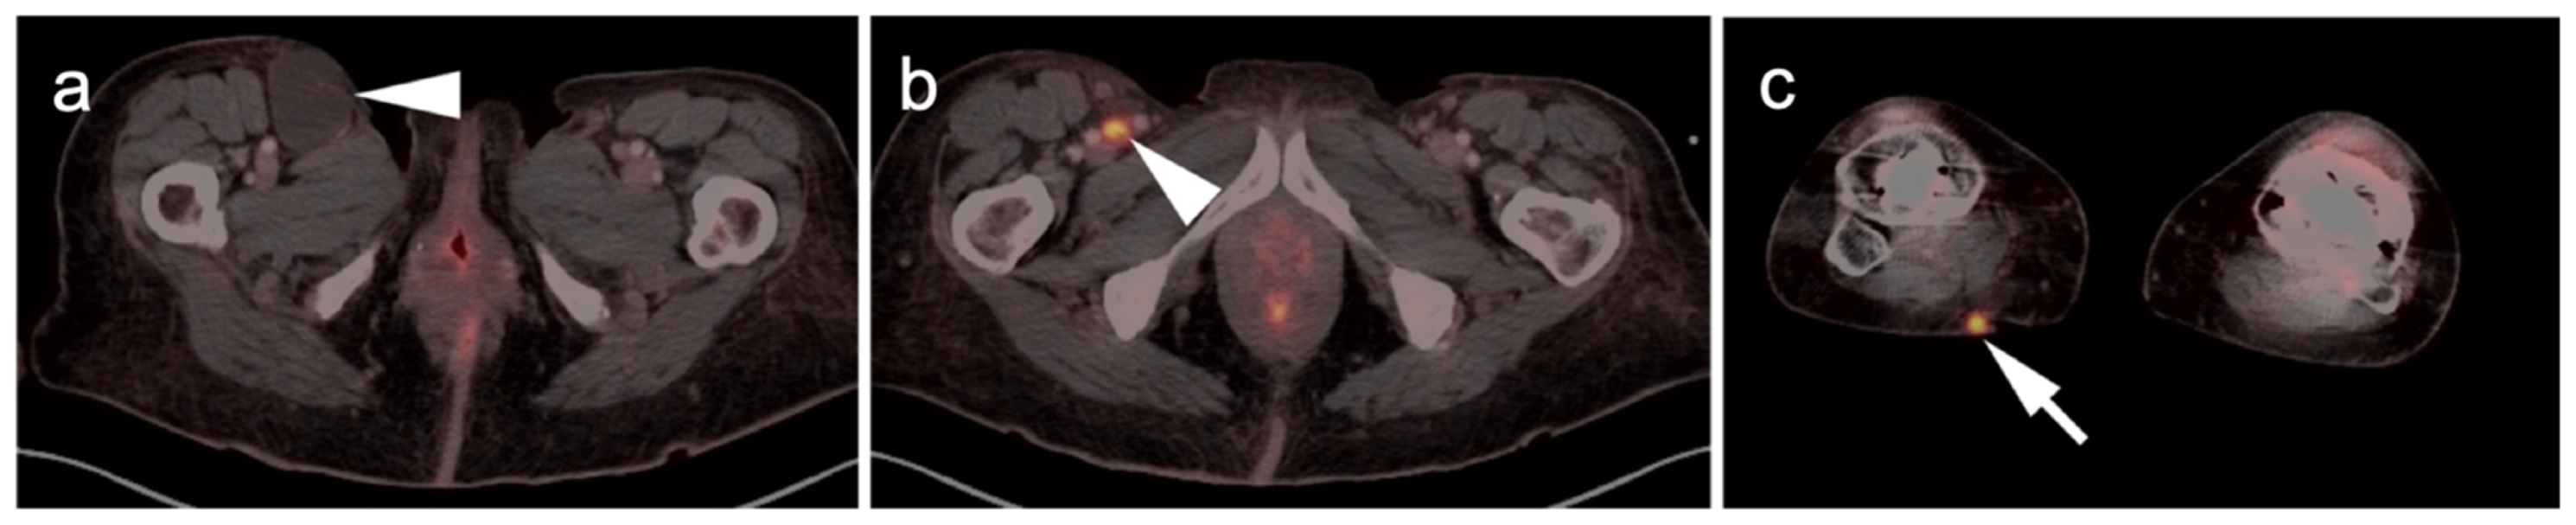

3. Sarcomas

3.1. Soft Tissue Sarcomas

3.1.5. Rhabdomyosarcoma

3.1.6. Liposarcoma

3.1.7. Synovial Sarcoma

3.1.8. Nerve Sheath Tumors

3.2. Bone Sarcomas

3.2.1. Chondrosarcoma

3.2.2. Osteosarcoma

3.2.3. Ewing Sarcoma